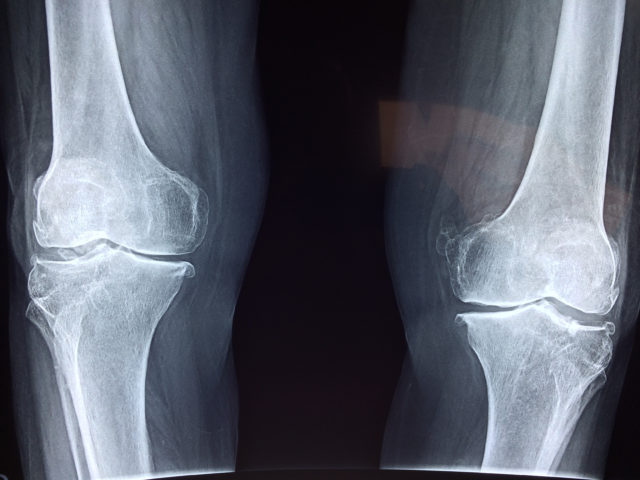

Knee pain afflicts millions of people every day and is a common condition we treat at Texas Orthopedics. In fact, as many as 1 in 4 Americans suffer from chronic knee pain. We asked board certified orthopedic surgeon Robert Blais, …

More than 23 percent of adults in the U.S. have arthritis, according to the Centers for Disease Control and Prevention (CDC). There is no cure for arthritis but many times the pain, stiffness and swelling in the joints caused by …

The Centers for Disease Control and Prevention projects 63 million people in the United States have arthritis. Texas Orthopedics physicians diagnose and treat this painful, debilitating condition every day. In honor of Arthritis Awareness Month, Dr. Vilas Saldanha and Dr. …